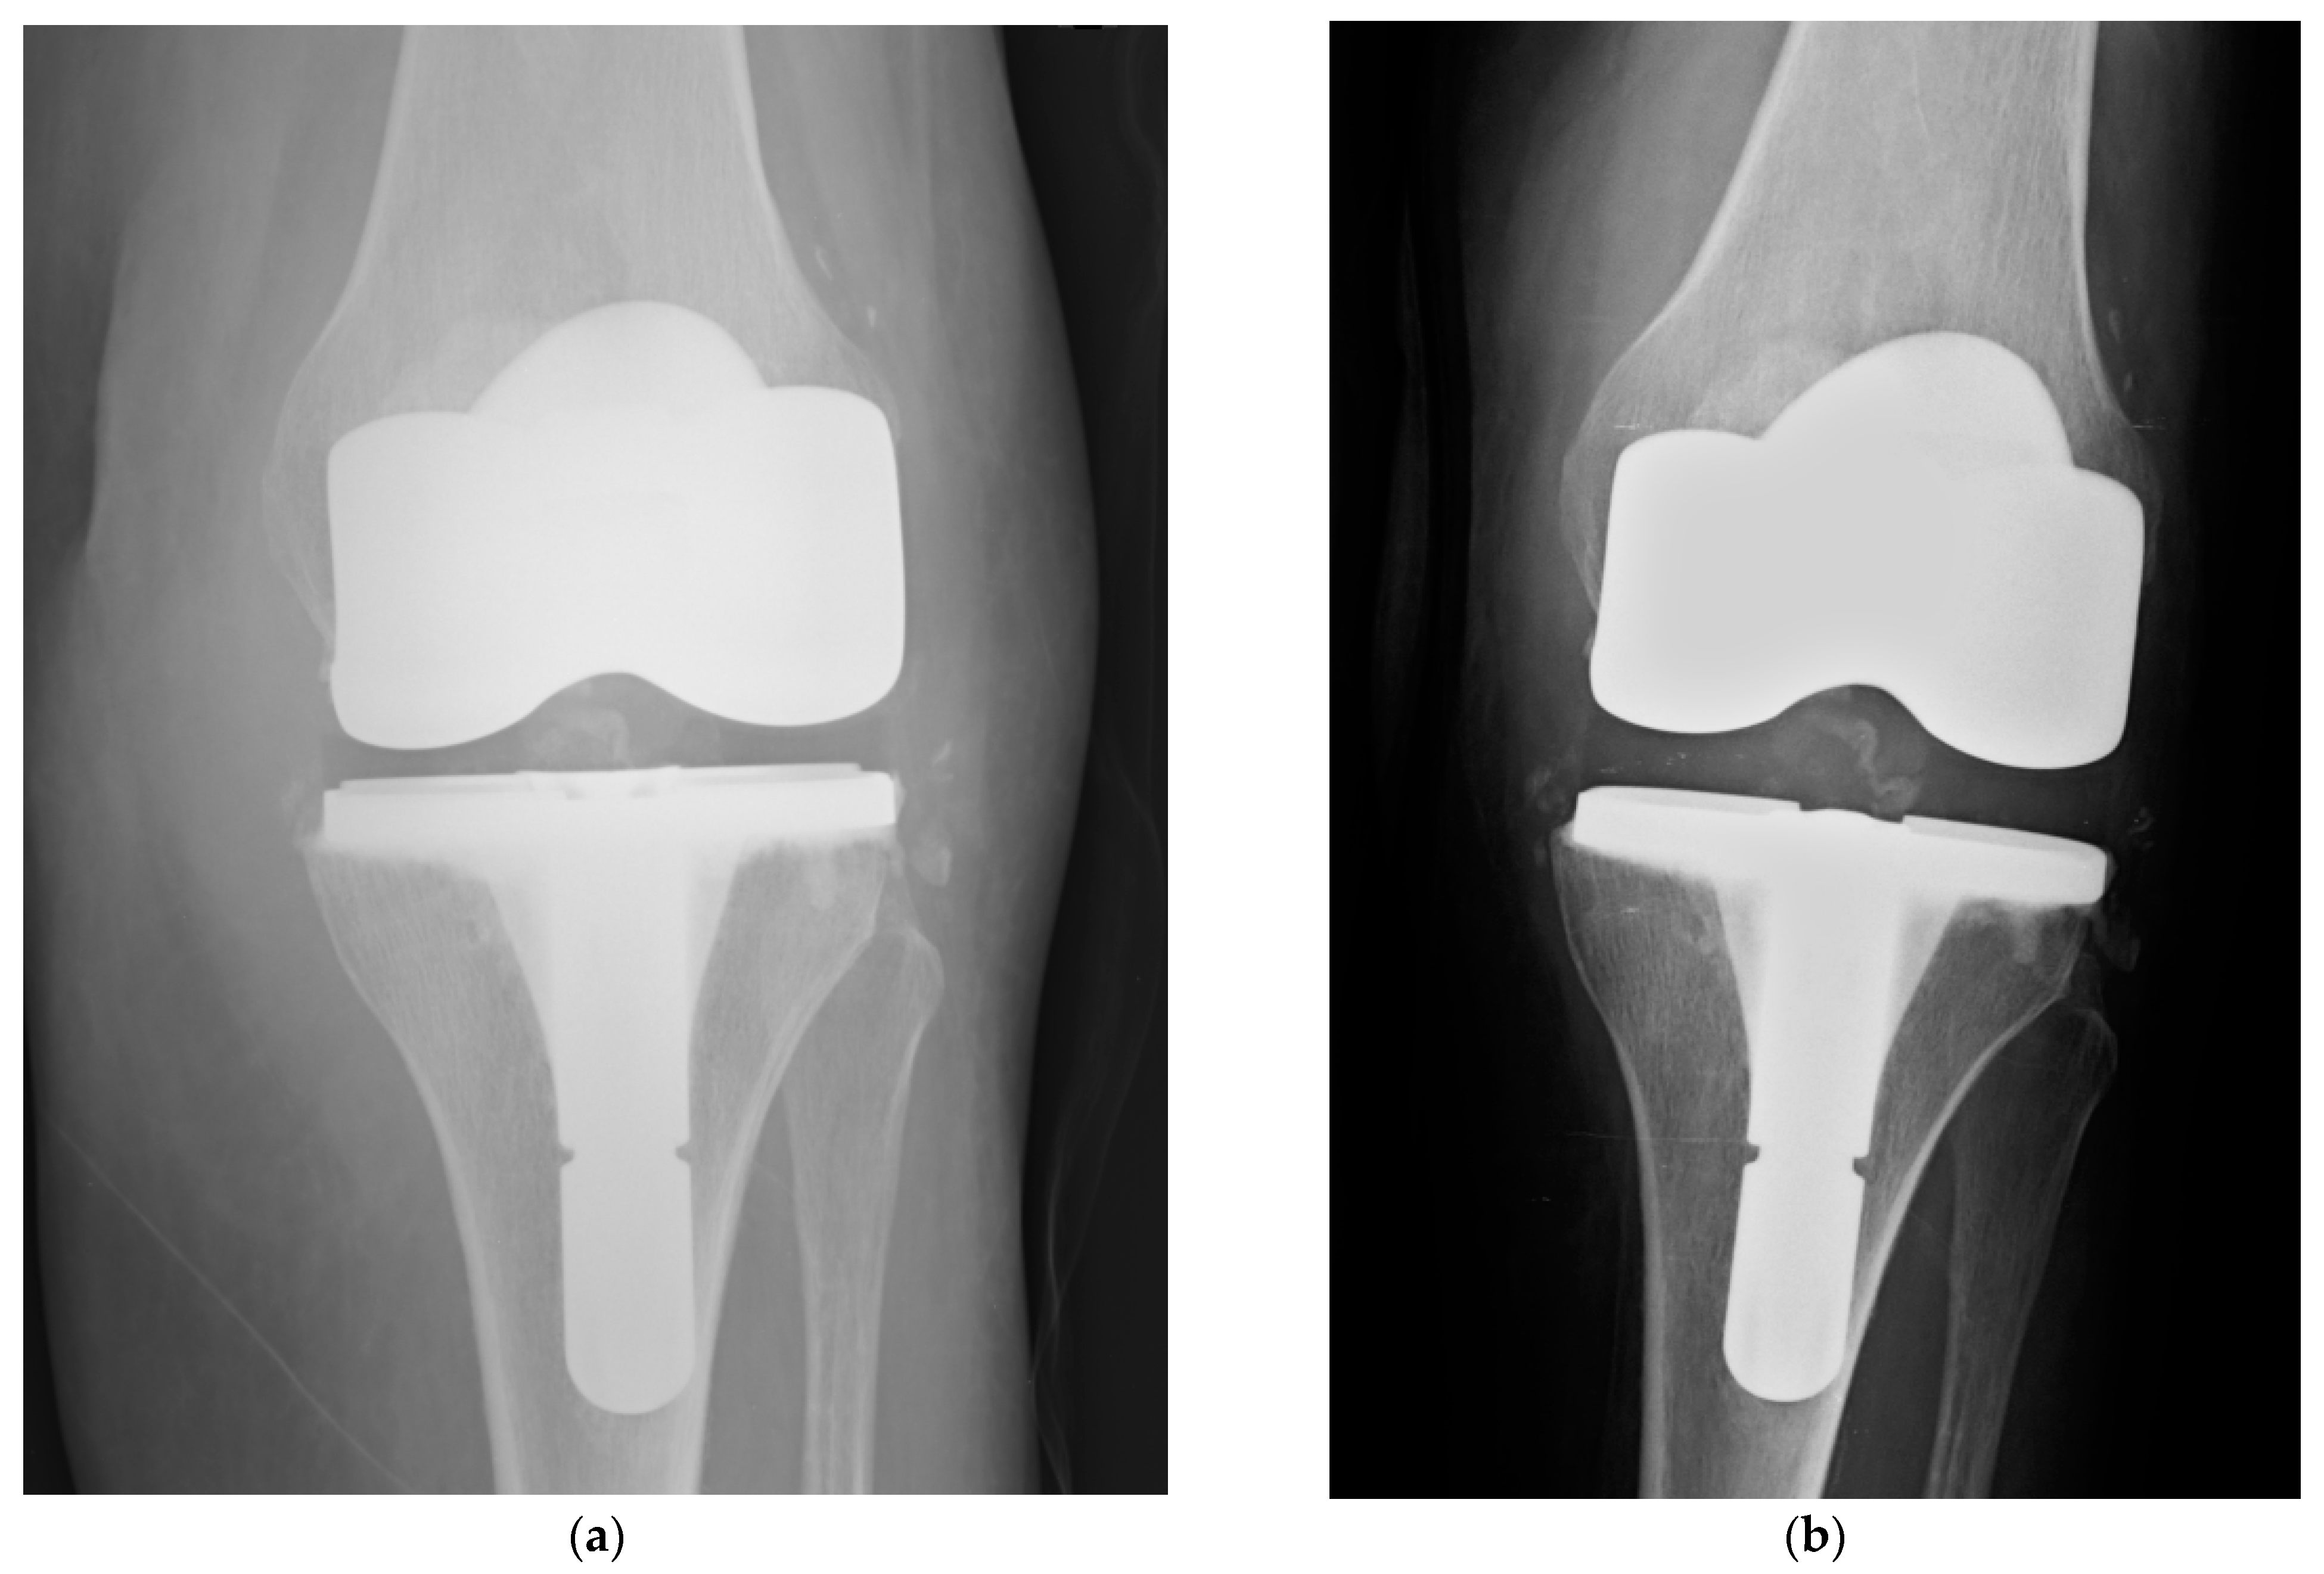

- Capuano, N.; Logoluso, N.; Gallazzi, E.; Drago, L.; Romanò, C.L. One-stage exchange with antibacterial hydrogel coated implants provides similar results to two-stage revision, without the coating, for the treatment of peri-prosthetic infection. Knee Surg. Sports Traumatol. Arthrosc. 2018, 26, 3362–3367. [Google Scholar] [CrossRef]

- Ferry, T.; Batailler, C.; Petitjean, C.; Chateau, J.; Fevre, C.; Forestier, E.; Brosset, S.; Leboucher, G.; Kolenda, C.; Laurent, F.; et al. The Potential Innovative Use of Bacteriophages Within the DAC® Hydrogel to Treat Patients with Knee Megaprosthesis Infection Requiring “Debridement Antibiotics and Implant Retention” and Soft Tissue Coverage as Salvage Therapy. Front. Med. 2020, 7, 342. [Google Scholar] [CrossRef] [PubMed]